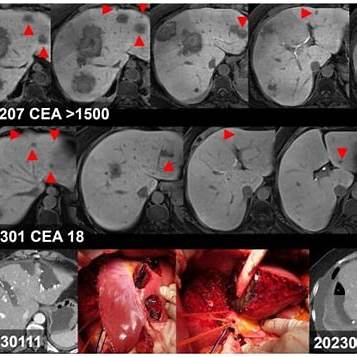

알프스 수술(ALPPS, Associating Liver Partition and Portal vein Ligation for Staged hepatectomy)은 대장암이 간으로 전이된 환자에서 간 절제술을 통해 생존율을 높이기 위한 2단계 수술법입니다.coloproctol.org+5KMA 저널+5KMA 저널+5

1. 1차 수술: 간의 일부를 절제하고, 남은 간을 분리한 후 **간문맥(portal vein)**을 결찰하여 **미래 간 잔여량(FLR)**의 성장을 촉진합니다.경향신문

2. 2차 수술: 약 2주 후, FLR이 충분히 성장하면 나머지 간 전이 병변을 제거하여 모든 암 병소를 절제합니다.coloproctol.org+6경북뉴스+6경향신문+6